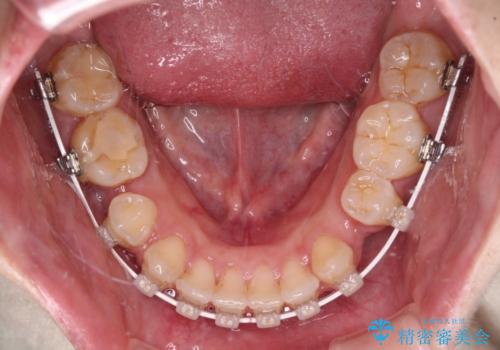

- 矯正装置

- 審美装置

- 治療計画

- 口元の突出感と上下前歯のズレを気にして来院された患者様です。

舌の突出癖により上下の前歯は非接触であり、更には奥歯の咬み合わせが非対称となっている状態でした。

舌のトレーニングを行わないと上下前歯の接触達成は困難であるため、トレーニングをしっかりと行っていただきながら、治療を進めて行くこととしました。

通常は上下左右の第一小臼歯4本を抜歯することになりますが、右側臼歯部の咬合が上顎前突気味であったため、下顎右側のみ第二小臼歯を抜歯し、ワイヤー装置にて矯正治療を行うこととしました。